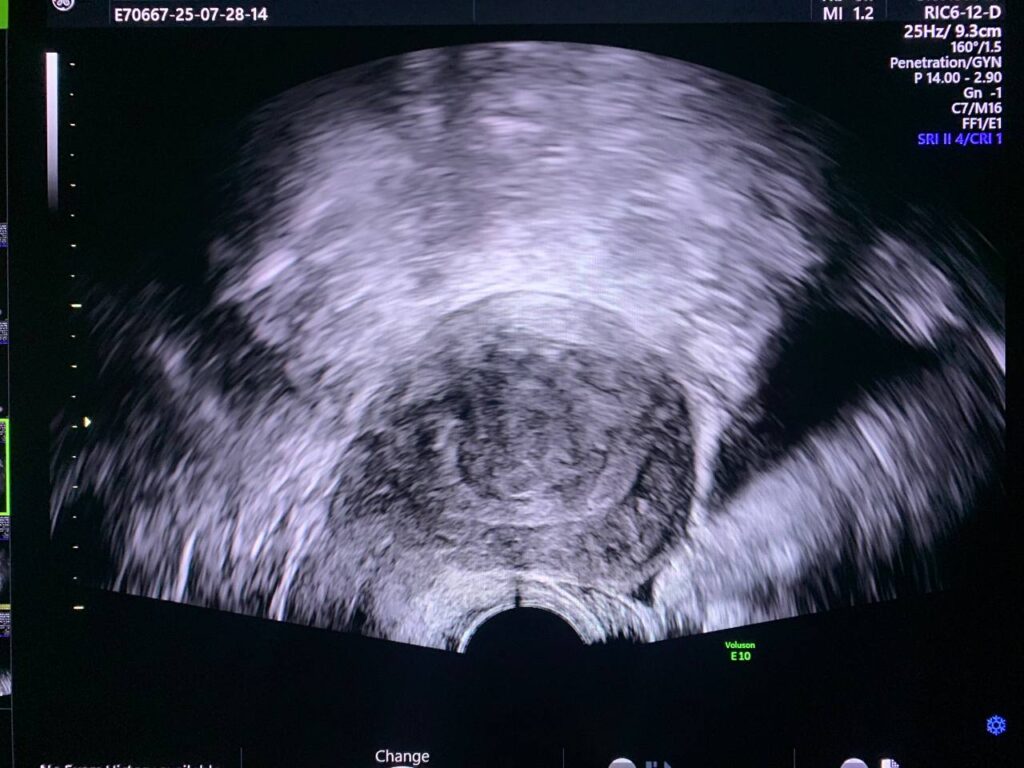

Bulky size, A/V uterus, endometrial lining thickness 3.6mm, displaced by submucosal intramural hyper vascular hypoechoic solid mass size about 33x31mm, could be fibroid ? , focal adenomyosis? , for further study to exclude other pathology.